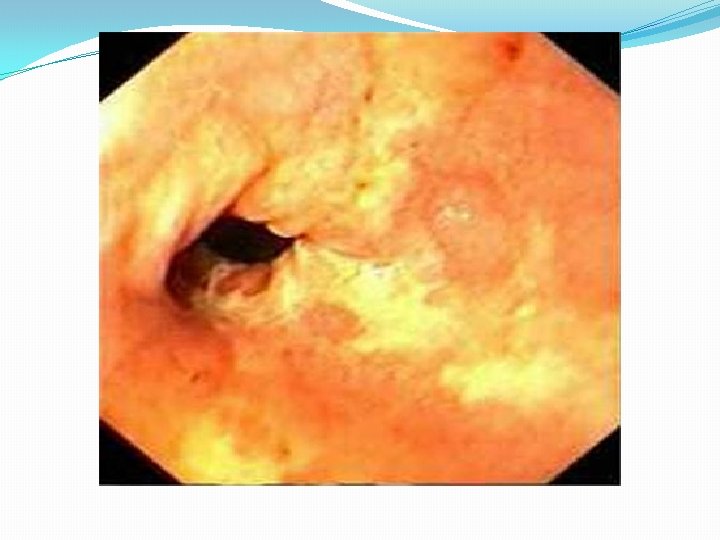

4. Endoscopy : allows diagnosis of erosive esophagitis and complications such as strictures or Barrett esophagus; biopsies can be taken. 5. Laryngotracheobronchoscopy : posterior laryngeal inflammation and vocal cord nodules. 6. Empirical antireflux therapy

Complications of GERD 1. Esophageal *Esophagitis and Stricture. * Barrett Esophagus *Adenocarcinoma 2. Nutritional: failure to thrive because of caloric deficits.